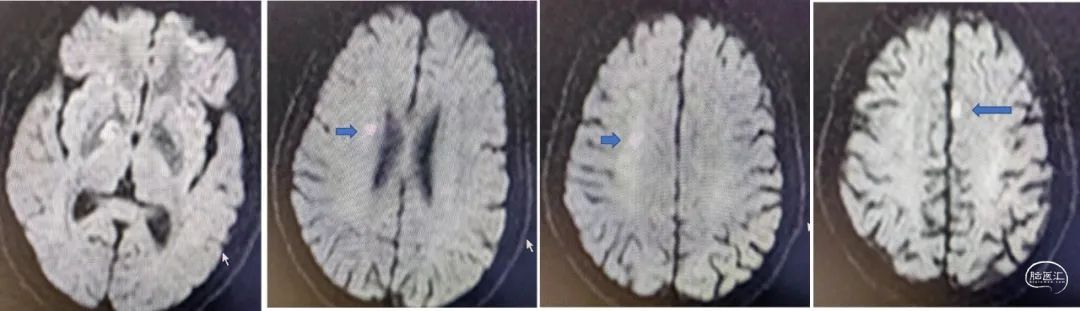

MRI+DWI

重要影像结论:右侧放射区、右侧基底节区、左侧额叶近大脑镰处多发急性梗死。

DWI

重要影像结论:右侧额颞枕顶叶多发急性期脑梗死灶。